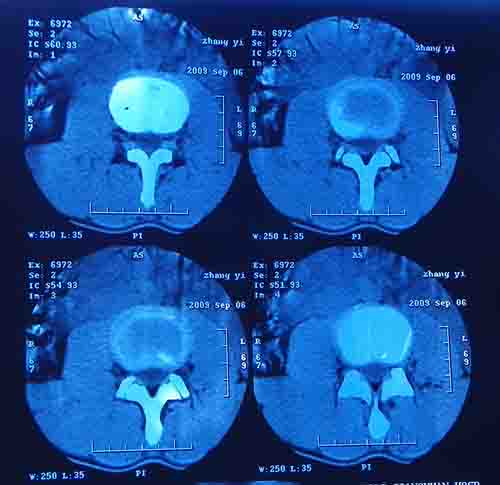

标题: CT22052:腰5/骶1椎间膨突出外,还有点异常,不知是什么东东 [打印本页]

标题: CT22052:腰5/骶1椎间膨突出外,还有点异常,不知是什么东东

腰5/骶1椎间膨突出外,还有点异常,不知是什么东东,请各位大虾帮忙看看(12骨窗最明显)

椎体后缘软骨结节